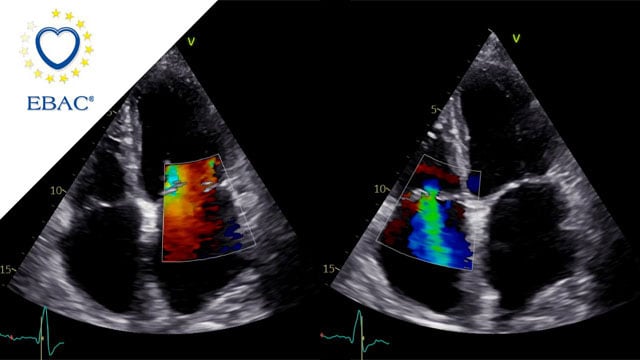

Multimodality imaging reveals fibro-calcific leaflet disease, restricted motion, and a short posterior leaflet, making him a suboptimal candidate for M-TEER and prompting consideration of transcatheter mitral valve replacement. How would you treat?